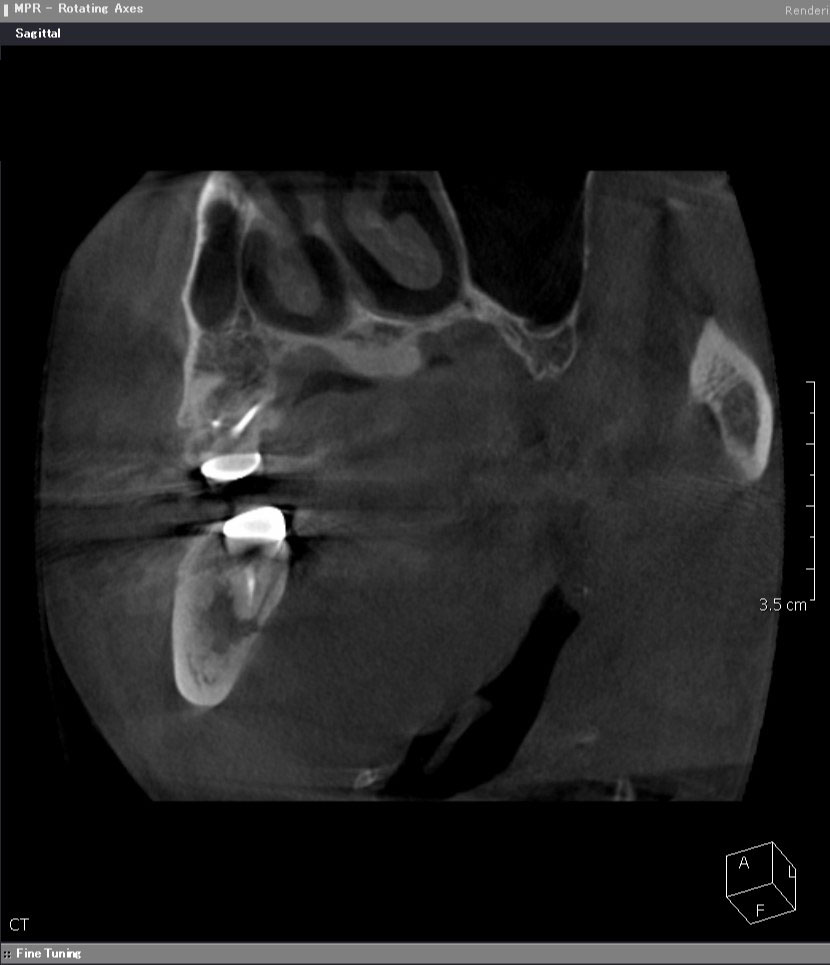

術前CT矢状断

近遠心的(手間から奥に向かって)に、根っこの先に化膿による大きな鶏卵状の境界明瞭な黒い骨透過像を認めます。ここまで大きいと、一般的には抜歯が適応となります。

根っこの先の黒い骨透過像(吸収像)をはっきりと認め、下顎の神経束(丸い玉状の像)ギリギリまで拡がっていることが分かります。このままにしていれば、顎の痺れが出現すると考えられます。